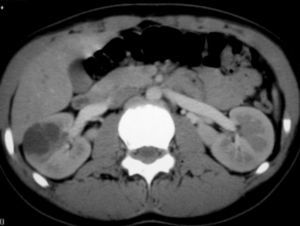

El sarcoma de células claras tuvo lugar en un niño de 2 años estudiado por masa abdominal, en el que se identificó una masa intrarrenal, de predominio necrótico y una adenopatía retrocava (fig. 8).

Fig. 8. Sarcoma de células claras. Tomografía computarizada abdominal con contraste intravenoso. Corte sobre polo inferior renal. Masa en riñón derecho, sólida, hipodensa, con gran crecimiento extrarrenal y que desplaza colon ascendente hacia delante (flechas). Adenopatía retrocava, hipodensa (A) de 3 cm.